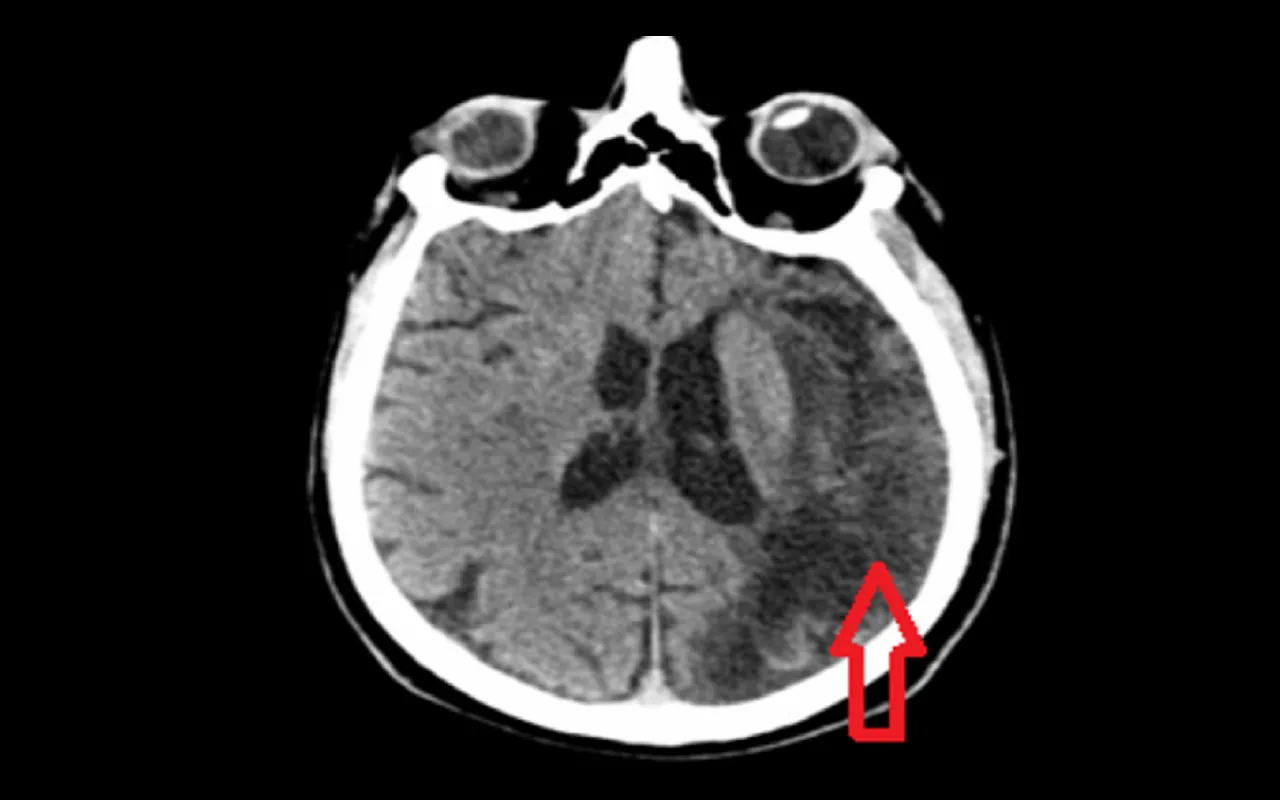

Tomografia komputerowa: Pierwsze badanie, które rozróżnia udar od wylewu

Po przybyciu do szpitala, jednym z pierwszych i najważniejszych badań diagnostycznych jest tomografia komputerowa (TK) mózgu. To badanie jest kluczowe, ponieważ pozwala szybko odróżnić udar niedokrwienny od krwotocznego. Na obrazie TK udar krwotoczny jest widoczny od razu jako obszar krwawienia, natomiast udar niedokrwienny, w początkowej fazie, może być mniej wyraźny. Ta informacja jest absolutnie niezbędna, ponieważ leczenie obu typów udaru jest diametralnie różne to, co pomaga w udarze niedokrwiennym, może być śmiertelnie niebezpieczne w przypadku krwotoku.